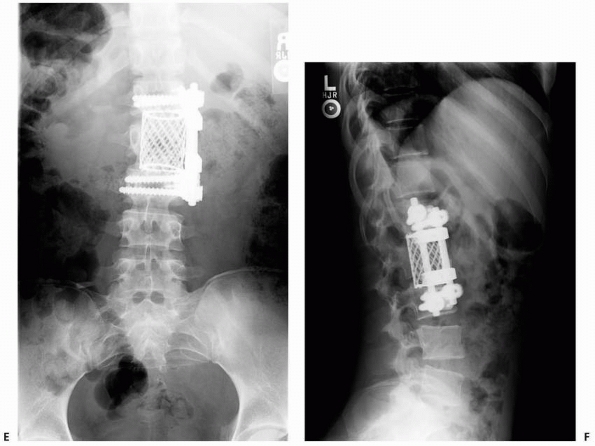

FIGURE 19-9 (Continued)

Given the lack of compliance and progressive kyphosis, the patient underwent anterior reconstruction with an iliac crest strut graft and plating (E,F). |